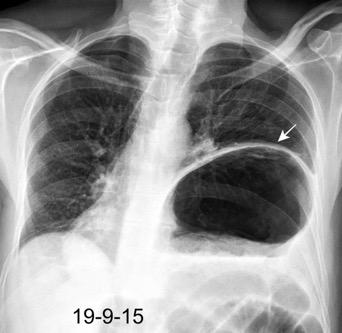

Parálisis frénica transitoria tras cirugía de válvula aórtica

Parálisis frénica transitoria post cirugía cardiaca (10%).

Puede acompañarse de atelectasia del LII.

Benjamin JJ et al. . Left lower lobe atelectasis and consolidation following cardiac surgery: the effect of topical cooling on the phrenic nerve. Radiology 1982